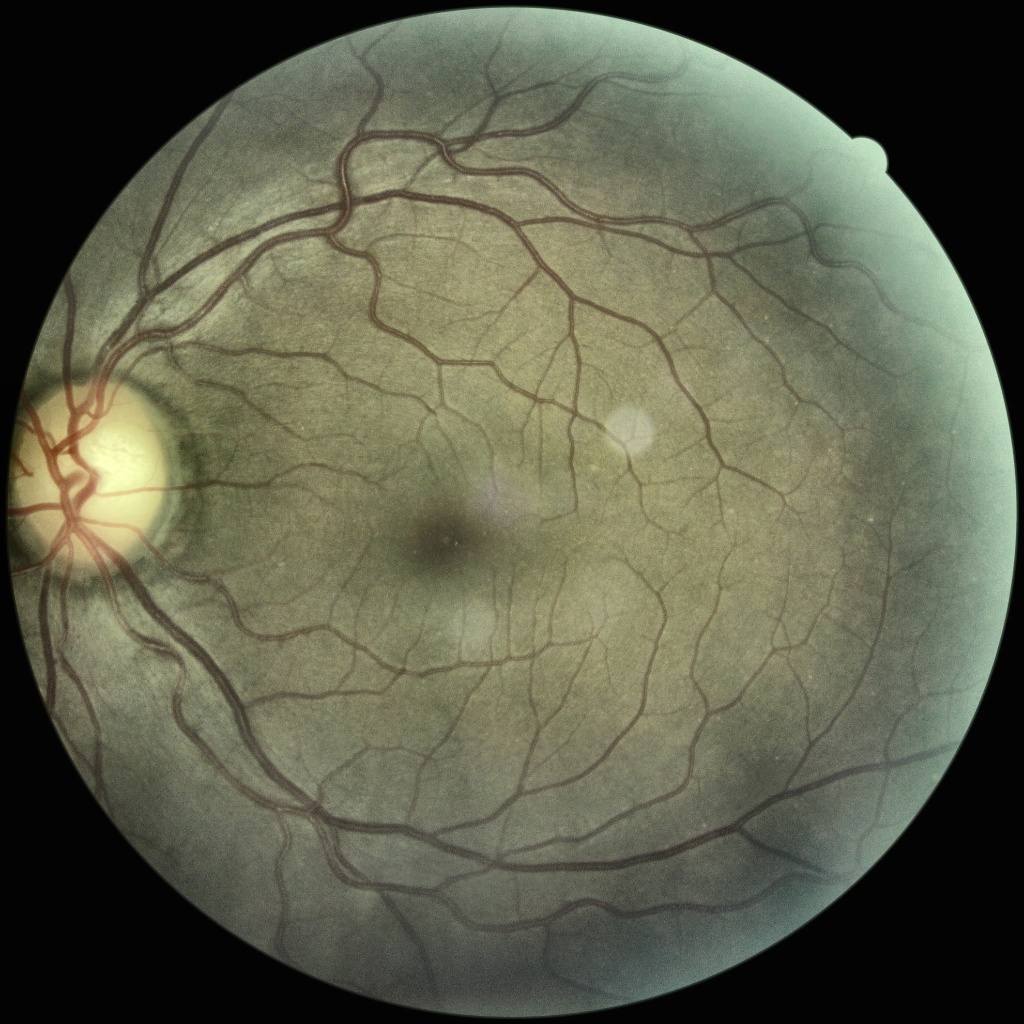

Timely diagnosis is the key to appropriate prognosis. Ophthalmologists usually detect DR by examining retinal fundus and looking for any signs of microaneurysms (bulging of blood vessels), blood leakage, and/or neovascularization [2]. While the indications of advanced stages of DR are rather prominent, these symptoms remain largely discrete in early stages. Figure 1 shows progress of DR from healthy to proliferative stage in Retinal Fundus Images (RFIs) taken from EyePACS dataset111https://www.kaggle.com/c/diabetic-retinopathy-detection/data. It can be observed from the figure that the difference between healthy and early stages of DR are very subtle and not readily discernible. Manual analysis of these images requires highly qualified and specialized ophthalmologists who may not be easily accessible in developing countries or remote areas of developed countries. Even when medical experts are available, large scale analysis of RFIs is highly time-consuming, labour-intensive and prone to human error and bias. Furthermore, manual diagnosis by clinicians is largely subjective and rarely reproducible and, therefore, inter-expert agreement for a certain diagnosis is generally very poor.

Refer to caption

(a) (a) Healthy

(b) (b) Mild

(c) (c) Moderate

(d) (d) Severe

(e) (e) Proliferative

Figure 0: Progression of diabetic retinopathy from healthy to proliferative stage is subtle and gradual. Images are taken from EyePACS train set.